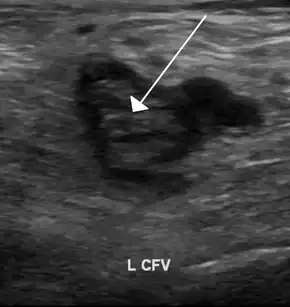

- An ultrasound with a blood clot visible in the left common femoral vein. (The common femoral vein is distal to the external iliac vein.)

Compression ultrasonography for suspected deep vein thrombosis is the standard diagnostic method, and it is highly sensitive for detecting an initial DVT.[118] A compression ultrasound is considered positive when the vein walls of normally compressible veins do not collapse under gentle pressure.[39] Clot visualization is sometimes possible, but is not required.[119] Three compression ultrasound scanning techniques can be used, with two of the three methods requiring a second ultrasound some days later to rule out the diagnosis.[118] Whole-leg ultrasound is the option that does not require a repeat ultrasound,[118] but proximal compression ultrasound is frequently used because distal DVT is only rarely clinically significant.[117] Ultrasound methods including duplex and color flow Doppler can be used to further characterize the clot[117] and Doppler ultrasound is especially helpful in the non-compressible iliac veins.[119]